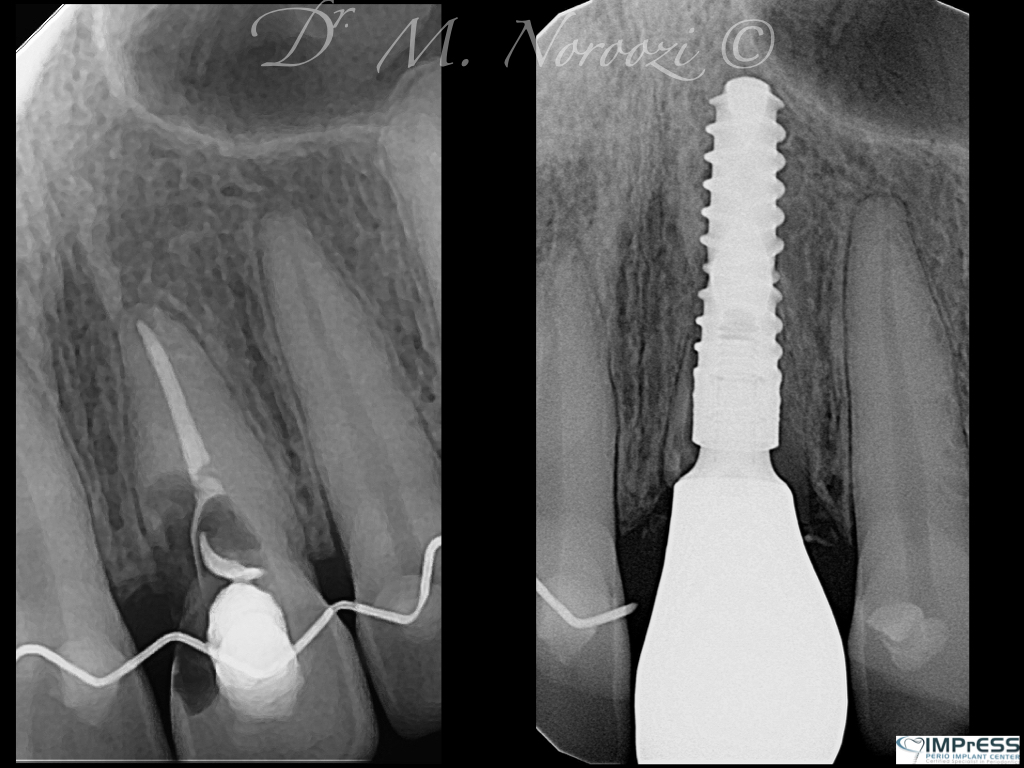

Immediate Implant Placement in Molar Extraction Site

immediate implant placement in molar site Dr. Noroozi